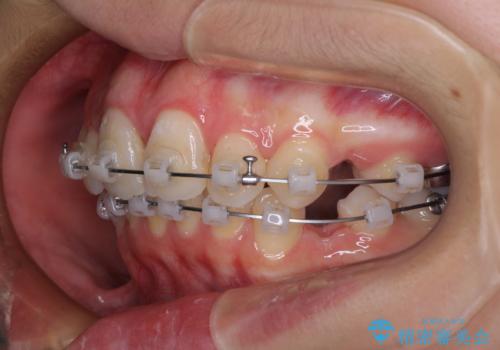

- クリアブラケット

- 1年9ヶ月

高校生ということもあり、治療期間は2年を切るスピードでした。